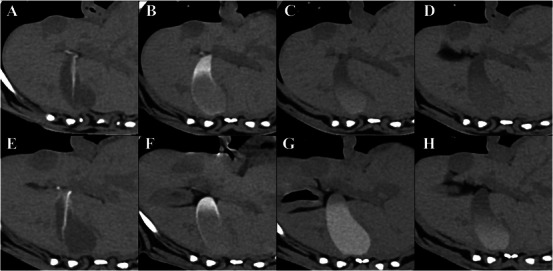

Vicarious excretion is a nonrenal pathway of excretion for intravenously injected iodinated contrast media, with a limited understanding of its influencing factors and imaging features. In this prospective pilot study, gallbladder opacification (GBO) and small intestinal luminal opacification (SILO) were assessed to identify vicarious excretion patterns following intravenous contrast media administration for CT in clinically healthy dogs. Eight beagles were studied using a crossover method, divided into fed and fasted groups. The fed group was fed at 5 and 13 h after the first CT scan, while the fasted group was fed only at 13 h. Noncontrast and postcontrast CT scans were performed at 90 s, 10 min, 1 h, 4 h, 12 h, and 24 h after iohexol injection. The GBO was subjectively scored from grade 0 to 5 based on the attenuation value and area of opacification. The SILO was evaluated subjectively based on contrast intensity (weak or marked) and distribution. The GBO was observed from 1 h after contrast injection. Significant differences were noted in median GBO scores within the groups at 4, 12, and 24 h on Friedman's test followed by the post hoc Wilcoxon signed-rank test. The scores were significantly higher in the fasted group at 12 h on the Wilcoxon signed-rank test. The SILO occurred 10 min after contrast administration, with various distributions. In conclusion, GBO and SILO can be observed during delayed CT phases, and fasting increases the intensity and duration of GBO in clinically healthy dogs. These findings should not be interpreted as pathological changes.

静脉注射碘造影剂的替代排泄是一种非肾性排泄途径,对其影响因素和影像学特征的了解有限。在这项前瞻性先导研究中,对临床健康犬的胆囊混浊(GBO)和小肠腔混浊(SILO)进行评估,以确定静脉注射造影剂后的替代排泄模式。8只小猎犬采用交叉实验方法进行研究,分为进食组和禁食组。饲喂组在CT首次扫描后5、13 h饲喂,禁食组仅在13 h饲喂。注射碘己醇后90 s、10 min、1 h、4 h、12 h、24 h分别进行非对比和对比后CT扫描。根据衰减值和混浊面积对GBO进行0 ~ 5级主观评分。根据对比强度(弱或明显)和分布对SILO进行主观评价。注射造影剂1 h后观察GBO。在弗里德曼检验和事后Wilcoxon符号秩检验中,4、12和24小时组内GBO得分中位数有显著差异。在12小时的Wilcoxon sign -rank检验中,禁食组的得分明显更高。SILO发生于给药后10分钟,且分布不同。综上所述,在CT延迟期可以观察到GBO和SILO,在临床健康犬中,禁食可以增加GBO的强度和持续时间。这些发现不应被解释为病理改变。